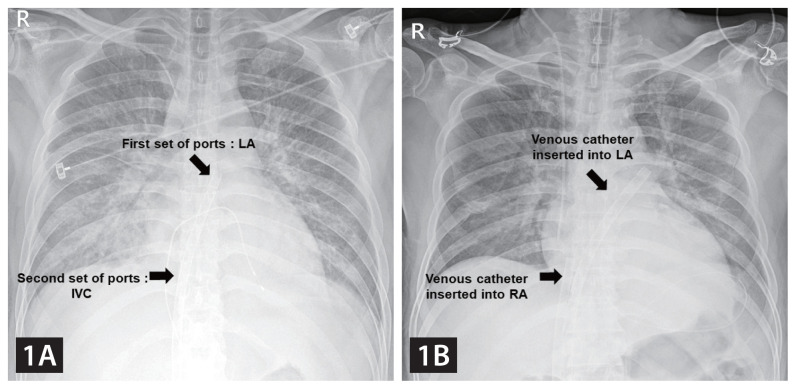

使用新型双心房插管进行股静脉-动脉体外膜肺氧合,以实现静脉引流和左心室通气。

Femoral veno-arterial extracorporeal membrane oxygenation with a novel biatrial cannula for venous drainage and left ventricular venting.